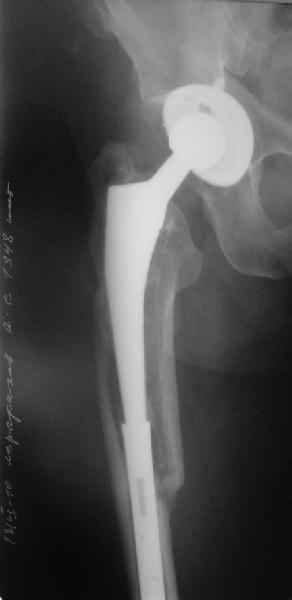

Произведено закрытое удлинение ножки эндопротеза с помощью ретроградного интрамедуллярного стержня. Продолжительность операции 3 часа. Два из них закрытое восстановление длины бедра диистрактором

таз-бедро.

Пациента удалось осмотреть недавно. Достигнутый результат сохраняется. Перелом бедра сросся. Конечность опорная и безболезненная, ходит без трости. Ножка, похоже, реинтегрировалась, как и надеялись. Снимки и фото в приложении. Комментарии приветствуются.

Надо ли что-то делать дальше, как полагаете? Убрать винты? Убрать "удлинитель ножки"? Или оставить все, как есть? Спасибо заранее.